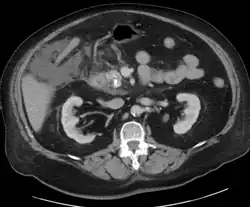

For imaging, abdominal ultrasound is convenient, simple, non-invasive, and inexpensive.[33] It is more sensitive and specific for pancreatitis from gallstones than other imaging modalities.[31] However, in 25–35% of patients the view of the pancreas can be obstructed by bowel gas making it difficult to evaluate.[30]

A contrast-enhanced CT scan is usually performed more than 48 hours after the onset of pain to evaluate for pancreatic necrosis and extrapancreatic fluid as well as predict the severity of the disease. CT scanning earlier can be falsely reassuring.[34]

ERCP or an endoscopic ultrasound can also be used if a biliary cause for pancreatitis is suspected.